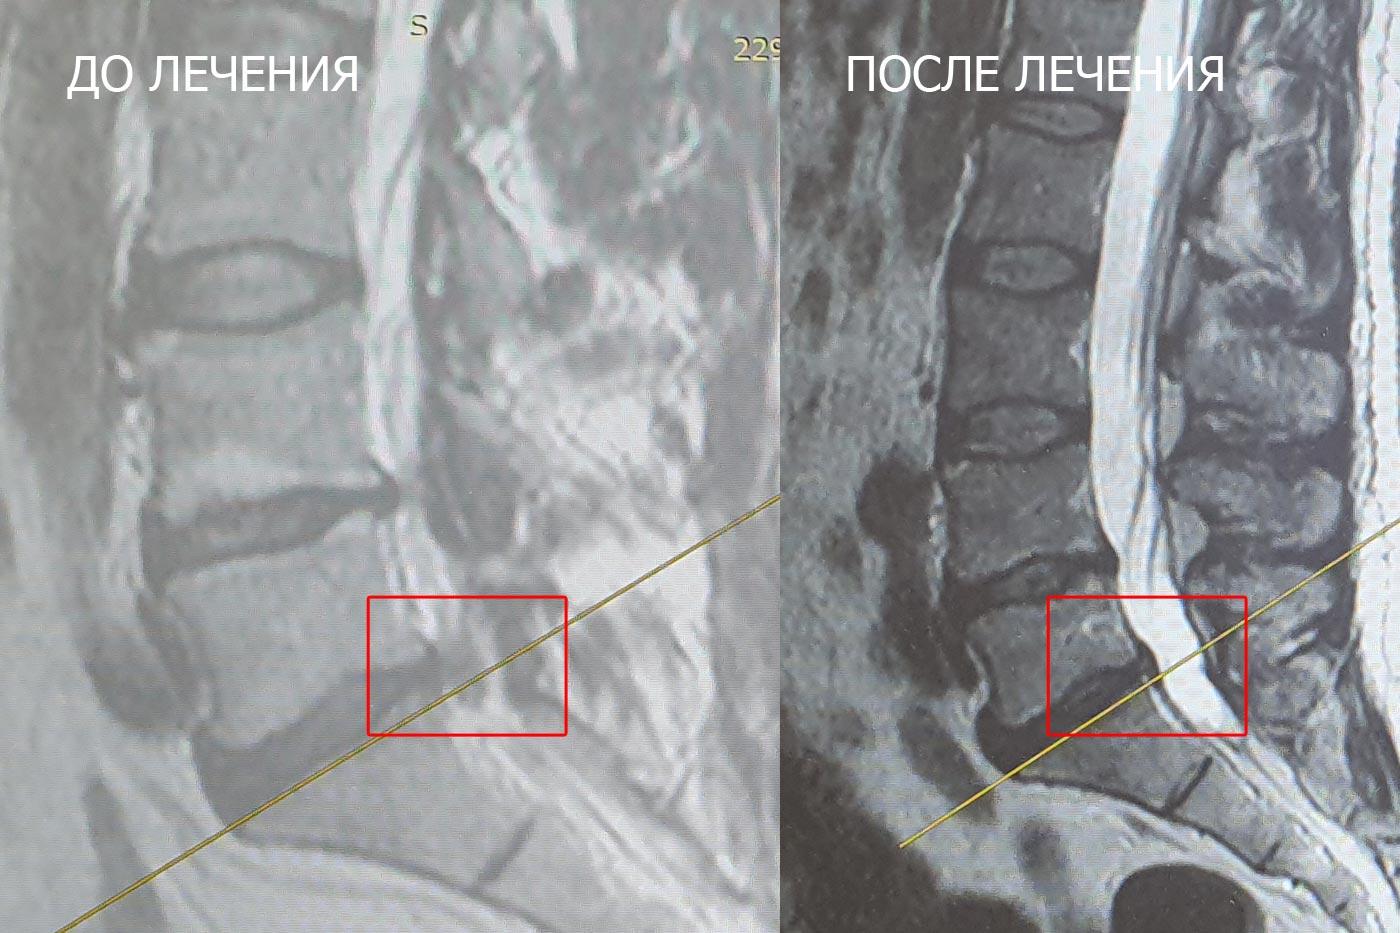

И вот результаты:

Клинически — 100% улучшение. Боли в спине и ноге полностью исчезли.

По МРТ — резорбция более 60% грыжи. И процесс продолжается — мы ожидаем ещё лучший результат на следующем контроле.

Честно говоря, этот случай стал приятным удивлением даже для нашей команды: при изначально низких ожиданиях организм ответил на терапию впечатляюще.